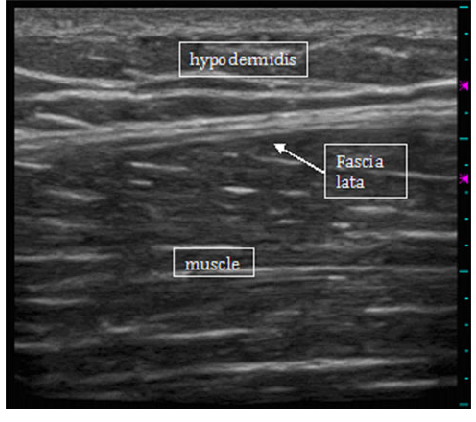

ultrasound: skeletal muscle

Hypoechoic fiber bundles interspersed with hyperechoic stromal connective tissue

ultrasound: fascia

Thin, hyperechoic (bright) structure